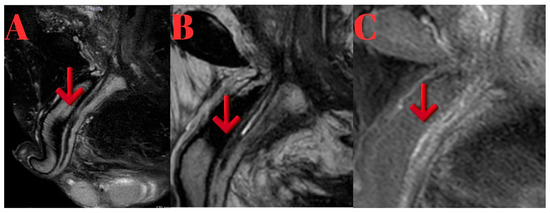

Background/Objectives: Conventional imaging modalities are often inadequate for evaluating the proximal extent of anterior obliterative urethral strictures. Magnetic Resonance Imaging (MRI), with its superior soft tissue resolution, provides detailed anatomical insights and significantly contributes to surgical planning in such cases. Methods: Four male patients aged 26–63 years with anterior obliterative urethral strictures were evaluated using MRI in addition to conventional imaging. All MRI scans were performed following a modified Joshi protocol. Clinical data, MRI findings, and surgical outcomes were retrospectively reviewed. Results: MRI successfully delineated stricture length, location, periurethral fibrosis, and proximal urethral status in all cases, correlating well with intraoperative findings. Case 1 showed a 2 cm proximal bulbar obliteration, excised with end-to-end anastomosis. Case 2 had a 2.5 cm distal bulbar stricture, managed similarly. Case 3 revealed multi-segmental strictures, treated with a combination of anastomosis, graft, and Kulkarni urethroplasty. Case 4 demonstrated a rare 9 cm distal penile obliteration with preserved proximal urethra, treated with anastomotic repair. MRI provided critical anatomical detail for surgical decision-making. Conclusions: MRI is a valuable imaging modality for the evaluation of anterior obliterative urethral strictures, particularly when the proximal extent of the stricture cannot be visualized with conventional imaging techniques. In our case series, MRI enabled precise delineation of the stricture length and surrounding anatomical structures, which was critical for selecting the most appropriate surgical approach. Full article

Figure 1